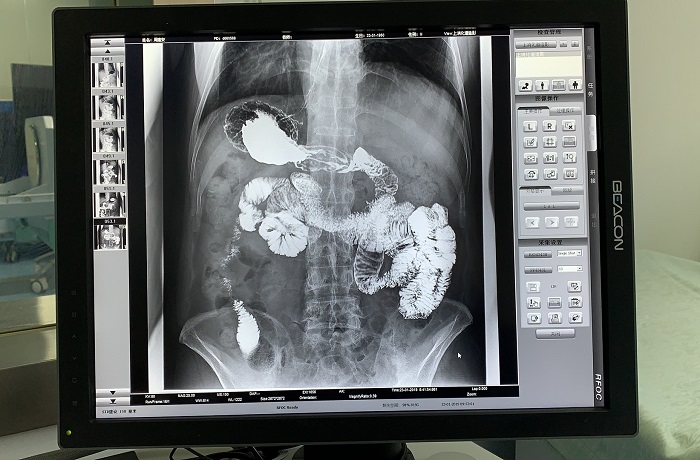

除鋇劑灌腸之外,動(dòng)態(tài)DRF還適用于胃腸道造影檢查,子宮輸卵管造影等。同時(shí),動(dòng)態(tài)DRF作為普通數(shù)字X光機(jī)使用,滿(mǎn)足全身各部位的數(shù)字化攝影檢查需求;作為具有透視功能的胃腸機(jī)使用,滿(mǎn)足全身各部位的數(shù)字化透視、透視下定位、透視下穿刺、透視下點(diǎn)片及簡(jiǎn)單的介入治療需求,全面適用于醫(yī)院體檢科、內(nèi)科、外科、骨科、創(chuàng)傷科、急診科等多個(gè)科室臨床診斷。

胃腸道造影高清影像